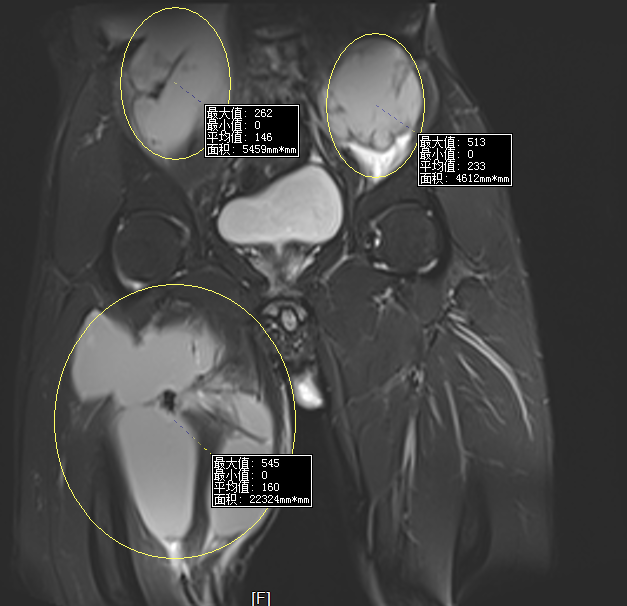

(通訊員  張保亮)小強(qiáng)(化名),男,32歲,永州人,近2年來(lái)覺(jué)得全身乏力,食欲下降,尤其是近半年來(lái)腰背部,臀部及大腿多處脹痛,在當(dāng)?shù)囟嗉裔t(yī)院就診,被診斷為骨結(jié)核,經(jīng)過(guò)1年多的治療,病情無(wú)好轉(zhuǎn)逐漸加重。1個(gè)月前經(jīng)人介紹來(lái)到永州市中心醫(yī)院北院,脊柱外科主任張勇主任醫(yī)師接診了該患者,仔細(xì)詢問(wèn)病人情況并檢查后發(fā)現(xiàn)該患者確實(shí)是患上了胸腰椎結(jié)核合并全身多發(fā)巨大流注膿腫,由于該患者近2年來(lái)四處求醫(yī)問(wèn)藥,治療很不規(guī)范,造成病情逐漸發(fā)展,脊柱死骨形成,多處巨大膿腫形成,抗癆藥也出現(xiàn)耐藥,治療起來(lái)十分棘手。如果不給予有效治療,該患者將面臨癱瘓甚至死亡的風(fēng)險(xiǎn)。

術(shù)前